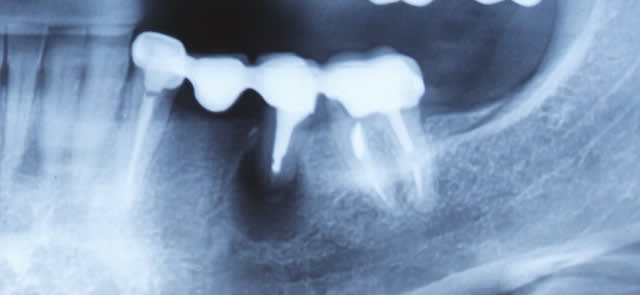

Le forage du tenon est bien bas. Lors de l'empreinte (tenon anatomique?) le confrère a blindé de light qui a fusé par l'apex? (ou éventuel canal accessoire ou perfo)

" Le forage du tenon est bien bas. Lors de l'empreinte (tenon anatomique?) le confrère a blindé de light qui a fusé par l'apex? "

oui oui , tu as vu ?, l' ic est plus long que le trou du foret calibré .

à mon avis lorsqu'il a foré , le bouchon de gutta est parti .

puis lors de l'empreint le light a fusé dans le peri- apex .

à cela tu rajoutes le ciment la fois d'apres , ça à fait un effet boeuf .

quand j'ai enlevé la petite bille de silicone , petite comme une tete d'epingle ,elle etait enveloppée dans un gluant blanc tout propre . un OEIL de bœuf !!brrrr :-)))

D'ailleurs le truc blanc en mésial de cette dent ("ds le septum)"c'est pas le bouchon de gutta qui aurait sauté et fait la malle ? :D